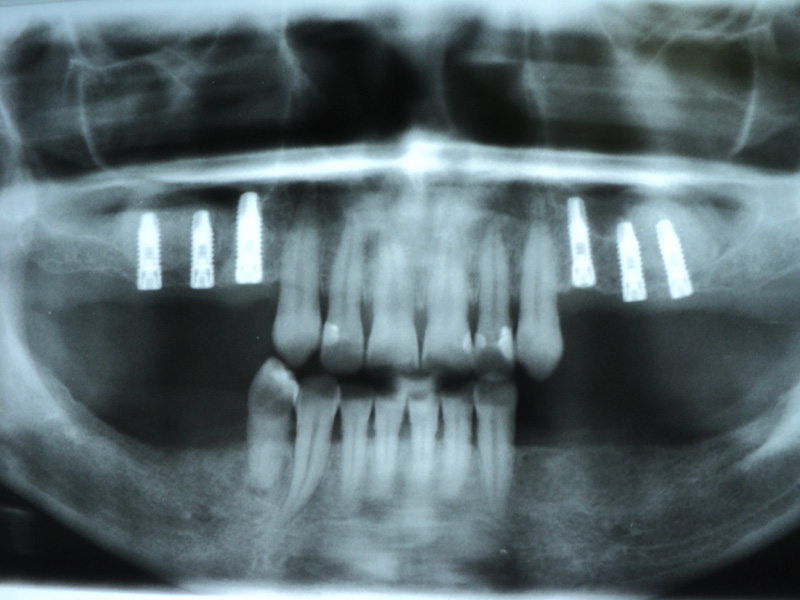

Implante - Galerie Foto

Caz II